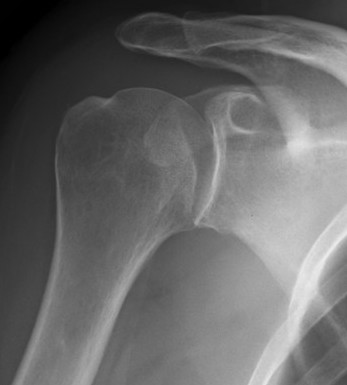

AP Xray

Abnormal overlap of humeral head on glenoid

Light-bulb sign - globular head secondary to internal rotation of the humeral head

Vacant Glenoid Cavity - > 6 mm space between humeral head and anterior rim of glenoid